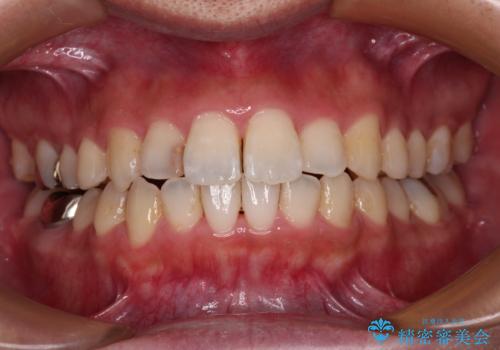

前歯のデコボコと突出感をマウスピース矯正できれいに

- 上下前歯のデコボコと突出感を気にして来院された患者様です。

目立たない装置を希望されたため、インビザラインによるマウスピース矯正を行うこととしました。

矯正治療後に銀歯をセラミックに替えたいとの要望があり、概ね歯列が整ったところで銀歯をセラミックに替え、仕上げにインビザライン1セットを使用して最終的に歯列を整えました。